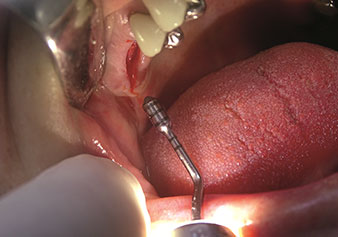

Une application souvent sous-estimée est l’extraction atraumatique de racines dentaires ou de fragments radiculaires dans le cadre d’une gestion alvéolaire. Les périotomes à denture fine, qui sont actuellement disponibles en deux versions (EX1 et EX2 de W&H), peuvent également être utilisés pour extraire facilement des dents qui ont subi un traitement endodontique spécifique préalable ou des racines ankylosées. On obtient des alvéoles d’extraction dans lesquelles à la fois les tissus durs et les tissus mous sont entièrement préservés.

Ceci instaure des conditions optimales pour un traitement implantaire ultérieur ou immédiat (Figures 1 et 2 fournies avec l'autorisation du Dr Torsten Conrad, Bingen

am Rhein).